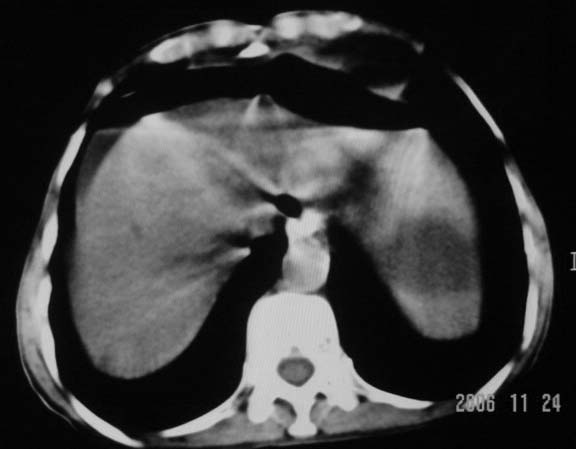

仰卧位见:肝前间隙及肝脾间隙内可见新月形气体密度影,边缘清楚,侧卧位见气体随体位改变而移动,ct值约-929hu。膈下、肝下间隙及部分肠间隙可见液性密度影。考虑:1、上腹部空腔脏器穿孔,以胃穿孔可能性大。2、少量腹水。

仰卧位见:肝前间隙及肝脾间隙内可见新月形气体密度影,边缘清楚,侧卧位见气体随体位改变而移动,ct值约-929hu。膈下、肝下间隙及部分肠间隙可见液性密度影。考虑:1、上腹部空腔脏器穿孔,结合临床,首先考虑胃穿孔可能性大。2、少量腹水

补充--肝门及肝肾间隙以见积气显示。

支持消化道空腔脏器穿孔(腹腔内大量游离气体影,小网膜囊内亦见气体影),少量腹水。